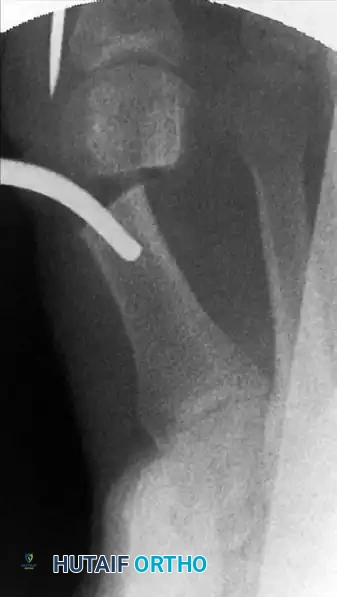

تصحيح الانحراف وتثبيت العظم

بعد اكتمال قص العظم، يجب إزاحة رأس العظمة نحو الخارج لتصحيح زاوية الانحراف. يتم إدخال أداة جراحية خاصة ذات تجويف عبر الشق الصغير وإلى داخل القناة العظمية.

إدخال الأداة الجراحية لتوجيه العظم

الأداة داخل القناة العظمية

يتم دفع السلك المعدني الذي تم وضعه مسبقا حتى يلتقي بالتجويف الموجود في الأداة الجراحية.

التقاء السلك بالأداة الجراحية

يستخدم الجراح هذه الأداة كرافعة لدفع رأس العظمة بلطف نحو الخارج وتصحيح التشوه، بينما يتحكم بيده الأخرى في إصبع القدم لضمان المحاذاة المثالية. يتم هذا الإجراء ببطء وحذر شديد لضمان عدم فقدان الاتصال بين جزئي العظم.

إزاحة العظم وتصحيح الانحراف

بمجرد الوصول إلى التصحيح المطلوب، يتم دفع السلك المعدني بعمق داخل القناة العظمية لتثبيت العظم في وضعه الجديد والمستقيم.

تثبيت العظم في الوضع الصحيح الجديد

يتم تأكيد الشكل النهائي للقدم وموقع السلك المعدني باستخدام الأشعة السينية. يعتبر التصحيح ناجحا عندما تكون العظام مصطفة بشكل مستقيم وسليم.

التأكيد النهائي لشكل القدم بالأشعة